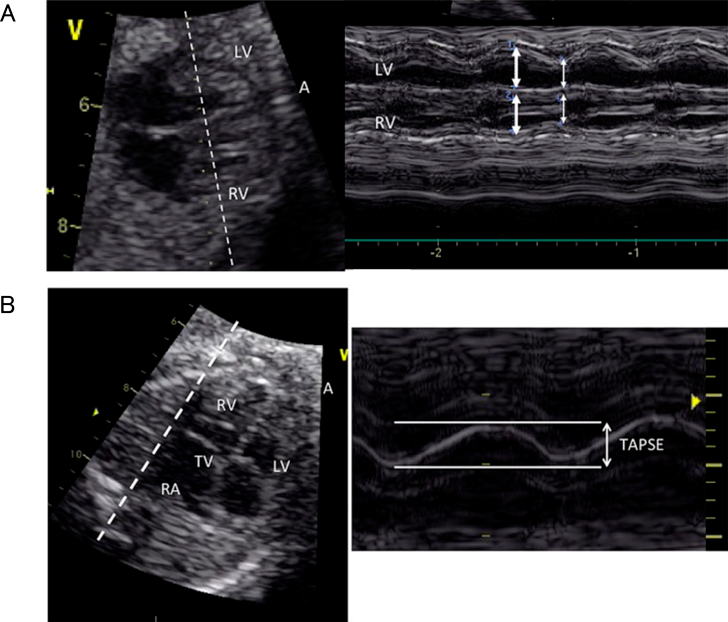

心機能の評価として最も直接的と考えられるのが心室収縮機能の評価であるが,胎児では胎位によって常に一定の角度で心臓の断面を描出できるわけではないこと,胎児の心電図が通常の方法では得られないことから,心室収縮機能の評価に用いることのできる方法は出生後と比較して限定される.現在用いられるのは心室内径短縮率(Fractional Shortening; FS)/心室駆出率(Ejection Fraction; EF)とdP/dt,収縮期僧帽弁/三尖弁輪移動距離(Mitral/Tricuspid Annular Plane Systolic Excursion; MAPSE/TAPSE),心室の統合機能評価として後述するMyocardial Performance Index(MPI)があげられる1, 5)

2.1 FS/EF

経胸壁心エコーでも古くから用いられているFSが心室収縮機能評価の指標の一つとして用いられており,最新の米国心エコー図学会の胎児心エコーガイドラインにも記載されている5).2Dエコーの四腔断面像もしくは短軸像,あるいはMモード法により計測される.ガイドライン1)ではMモード法での計測が示されている(Fig. 4A).いずれの計測法でも FS 心室拡張末期径-心室収縮末期径 心室拡張末期径 によって計算される.正常値は週数によらず一定で0.28~0.40とされる1)

Pediatric Cardiology and Cardiac Surgery 41(1): 11-19 (2025)

Fig. 4 Mモード心エコー法を用いた両心室のFractional Shortening(FS)の計測(A)と三尖弁輪収縮期移動距離(TAPSE)(B)の計測

文献21)より引用.

ただし,FSは立体的な構造をしている心室の一方向の機能しか評価できず,胎児では左室圧と右室圧が等圧で短軸像の心室中隔が扁平であること,右室は更に複雑な形態をしていることからより不正確と考えられることに注意が必要である.FSは現在の日本循環器学会の「循環器超音波検査の適応と判読ガイドライン」では左室収縮能の評価項目に記載されていない6)

2.2 MAPSE/TAPSE

左室・右室の長軸方向の収縮機能指標で,僧帽弁輪自由壁側/三尖弁輪自由壁側の長軸方向の移動距離がそれぞれMAPSE/TAPSEである.心尖が12時もしくは6時方向になるように四腔断面像を描出し,カーソルを心室中隔と平行になるように置いてM-mode法を用いて計測して算出される(Fig. 4B).これまでに複数の正常値(Z値)が報告されているほか,双胎間輸血症候群,胎児心不全,母体糖尿病などで検討されている8)

正常単胎の胎児ではMAPSEとTAPSEは在胎週数と共に大きくなり,MAPSEのほうがTAPSEより小さい.

なお,出生後の心エコーではTAPSEはセクタプローブを使用して心尖部四腔断面において三尖弁輪にカーソルを置いて計測するため,心室中隔には平行ではなく厳密には計測の方向が異なっている.